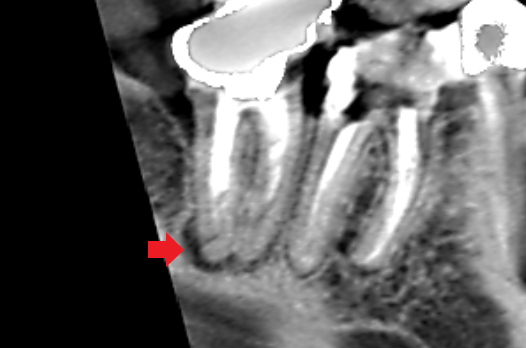

精密根管治療6カ月後の経過観察時の冠状断のCT画像です。遠心根の舌側にあった膿の影が消失し歯槽骨が再生してきています。